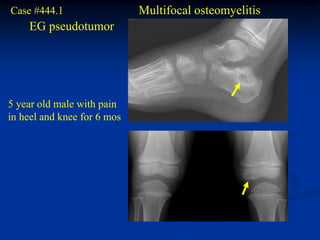

Case #444.1                  Multifocal osteomyelitis

EG pseudotumor

5 year old male with pain

in heel and knee for 6 mos

Sag T-1   T-2   Gad

Cor T-1        Sag T-2

Axial T-2